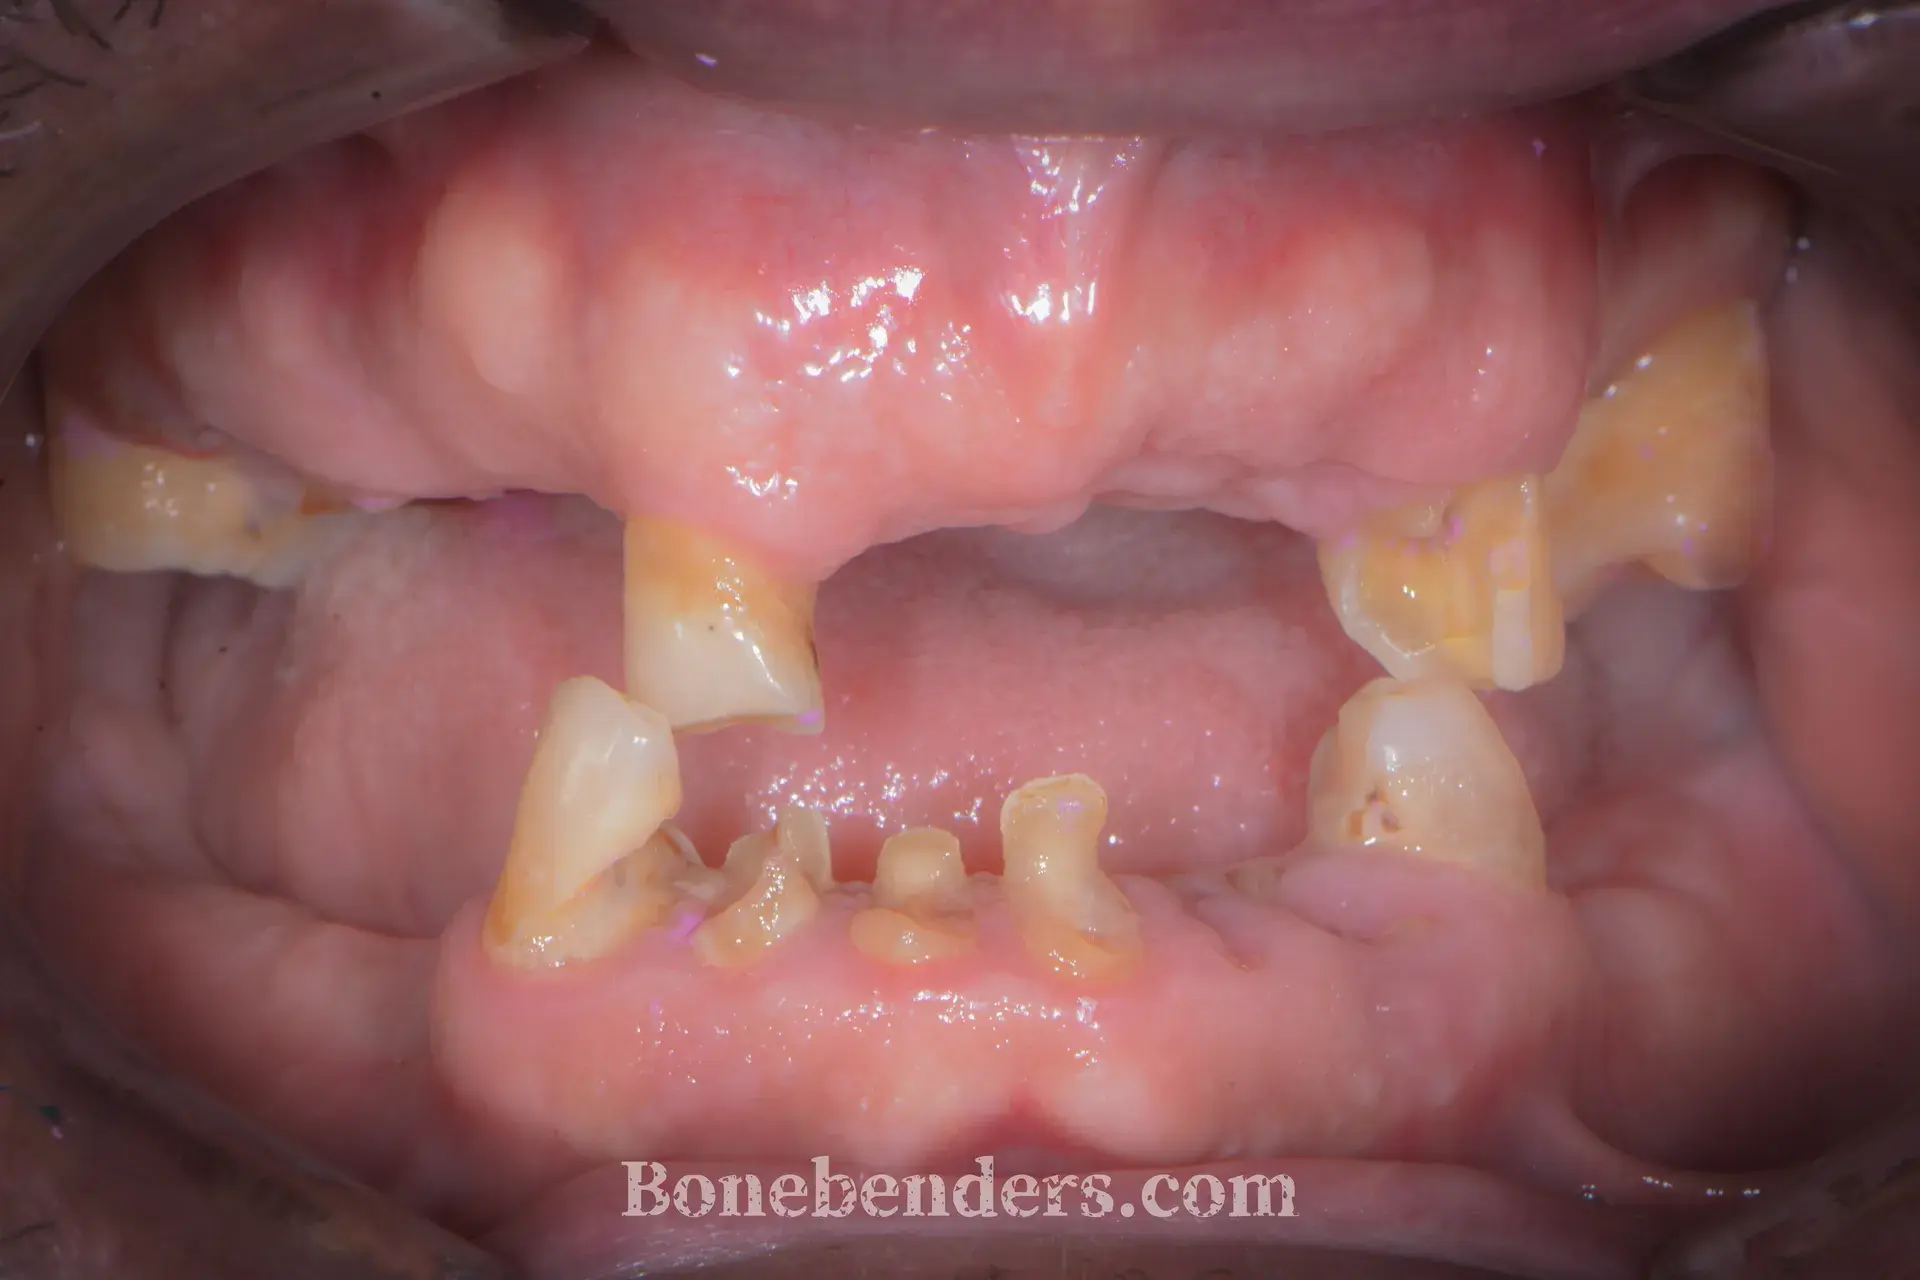

9 casi documentati con fotografie cliniche prima e dopo il trattamento. Ogni caso include la descrizione della tecnica, i tempi di guarigione e i riferimenti scientifici.